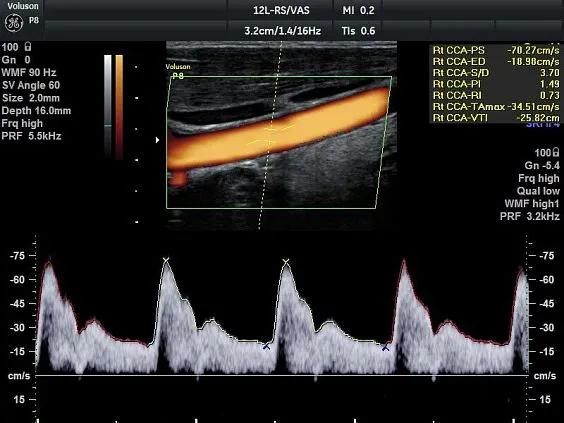

Клинические изображения

Voluson P8 одинаково уверенно справляется как с задачами в сфере женского здоровья (оценка развития плода, диагностика патологий малого таза), так и при сканировании сердца, сосудов, органов брюшной полости и поверхностных структур. Аппарат поддерживает современные технологии обработки изображения: HD-Flow™, Speckle Reduction Imaging (SRI), CrossXBeam™, что позволяет получить максимально чёткие и информативные данные даже в сложных клинических условиях.

- Ангиология;

- 12L-RS - линейный датчик 4-12 МГц для исследования поверхностно расположенных органов и структур, скелетно-мышечного аппарата, периферических сосудов, педиатри

- Усовершенствованное цветовое допплеровское картирование — для более детального исследования анатомии и функционального состояния сосудистой системы.